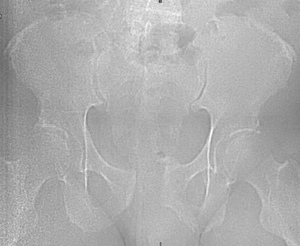

Chart review was undertaken to obtain basic demographic variables such as age, sex, smoking and diabetic history. Injury radiographs were reviewed to determine fracture type and Young-Burgess fracture classification. Preoperative and postoperative radiographs are demonstrated in figures 1A, 1B, 2A and 2B. Operative records were reviewed to determine which patients underwent screw removal and if any adverse intra-operative events occurred. Hospital charts and clinic charts were reviewed to document any postoperative complications and record pre and postoperative visual analog pain scales.